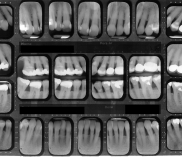

Chirurgia dentystyczna zajmuje się leczeniem operacyjnym jamy ustnej, zębów i tkanek otaczających. Znaczna większość zabiegów z zakresu chirurgii stomatologicznej jest wykonywana w znieczuleniu miejscowym .Dental Park jako jeden z nielicznych oferuje również wykonywanie zabiegów pod narkozą. Najpowszechniejszym zabiegiem z zakresu chirurgii stomatologicznej jest usunięcie zęba czyli ekstrakcja, ale chirurgia stomatologiczna to także zaawansowane zabiegi jak implanty czy wyłuszczanie torbieli kości.

Chirurg stomatolog posiada wieloletnie doświadczenie i w swojej karierze spotkał się z najtrudniejszymi przypadkami. W gabinecie wykonywane jest usuwanie zębów w znieczuleniu miejscowym oraz w narkozie co zapewnia całkowicie bezbolesny zabieg. Pracownia stomatologiczna usuwa zęby mądrości, złamane korzenie. Bardzo często naszymi pacjentami są osoby, które usuwają zęby ze wskazań ortodontycznych. Wykonujemy również zabiegi odbudowy kości jako przygotowanie do leczenia implantologicznego. Nasi pacjenci mogą zawsze liczyć na szybką pomoc w przypadku ropnia, ostrego bólu lub urazu. Chirurg stomatolog zajmuje się wszystkimi nawet najbardziej skomplikowanymi przypadkami.